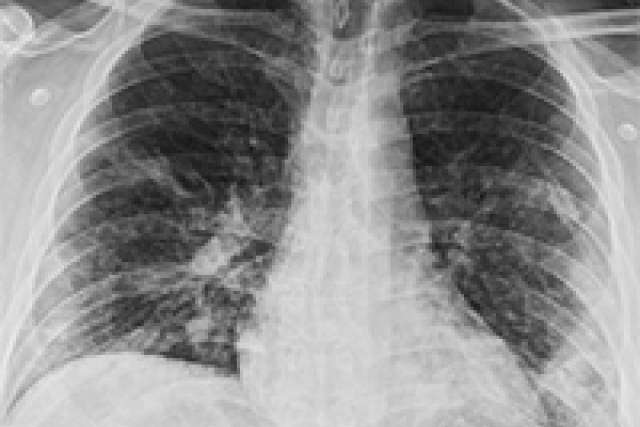

UCLA Chest X-Ray COVID-19 Guidelines

In the setting of the COVID-19 pandemic, chest imaging plays a very important role in the early diagnosis and the treatment planning for patients with suspected or confirmed COVID-19 chest infections. The UCLA Department of Radiology’s Thoracic and Acute Care Imaging (ACI) sections recognized the importance of the chest x-ray in this setting, as it is readily available in the community physician offices, urgent care clinics and hospital emergency departments. To help physicians and radiologists in these settings, they have developed the UCLA Chest X-Ray COVID-19 Guidelines.